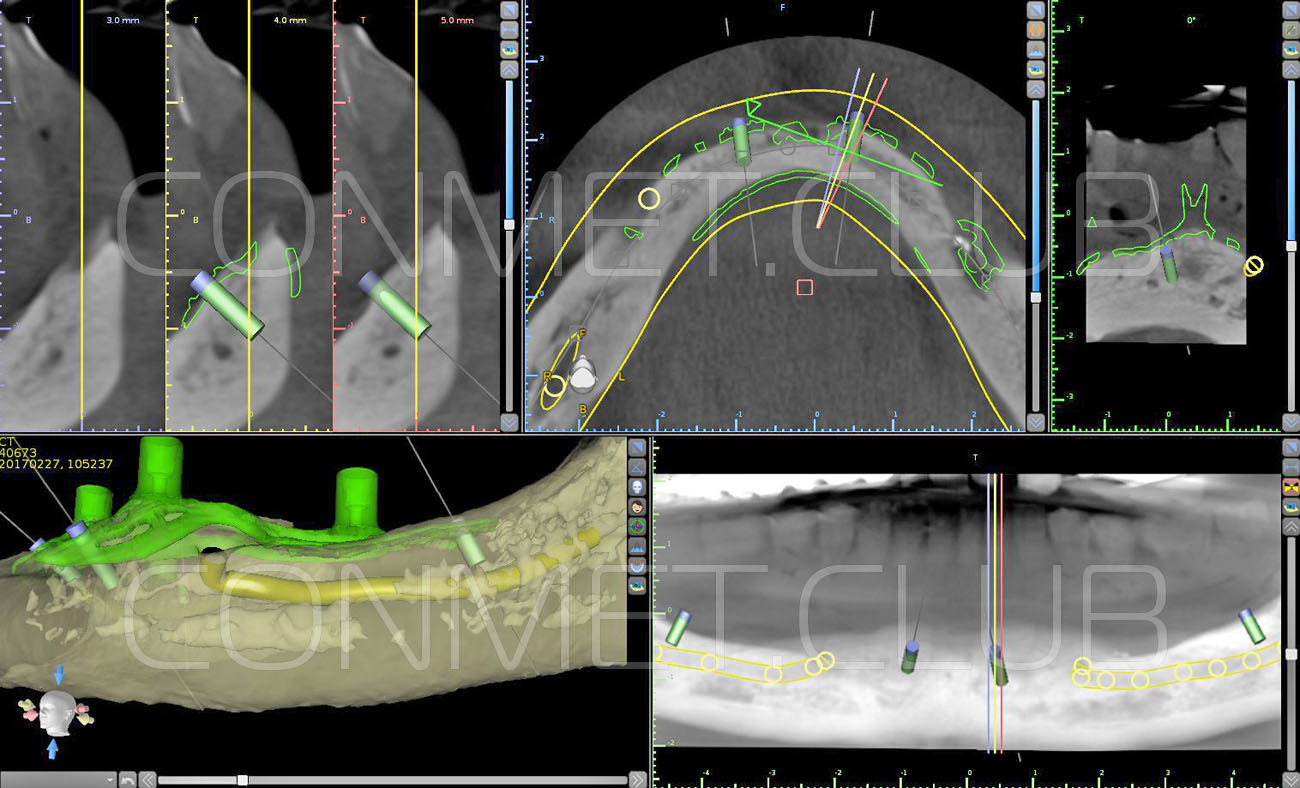

1. Пациенту было произведено МСКТ исследование нижней челюсти, с последующим созданием STL модели. В зуботехнической лаборатории был изготовлен восковой шаблон с искусственными зубами с учетом индивидуальных прикусных взаимоотношений (пока это делает зубной техник точно так же, как при изготовлении съемного пластиночного протеза).

2. После этого произвели компьютерное моделирование самого имплантата и фиксирующих элементов. Примечательно, что в абатментах, использовался отлично зарекомендовавший себя и проверенный десятилетиями интерфейс КОНМЕТ! В результате получили несколько специальных файлов, позволяющих не только сделать сам имлантат, но еще до операции изготовить и сами зубы. Данные файлы передали в изготовление на специальном 3D оборудовании.

Имплантат напечатали из особого, биосовместимого, медицинского титана на предприятии имеющим соответствующую медицинскую лицензию. Толщина имплантата составила 0,8 мм, а вес всего несколько грамм!

Сама же операция длиться 20-50 минут в зависимости от количества утраченных зубов. В процессе этой операции, после проведенной местной анестезии, делается разрез на слизистой, она приподнимается и субпериостальный имплантат укладывается на кость. После этого рана фиксируется несколькими швами и все! Через 10-14 дней мягкие ткани срастаются и надкостница надежно удерживает имплантат на месте. Нет необходимости ждать несколько месяцев, как это бывает в случае с внутрикостными винтовыми имплантатами.

И это еще не все. Для того, чтобы имплантат оптимально взаимодействовал с костью на которую он опирается и надкостницей, которая покрывает его сверху, необходима особая структура поверхности имплантата. И тогда через некоторое время, имплантат стороной обращенной к кости прочно с ней срастается.

Одним из лучших вариантов такой поверхности является структура АНАТАЗ полученная путем атомарного осаждения двуоксида титана с особой кристаллической решеткой на поверхность имплантата (запатентована фирмой Конмет).